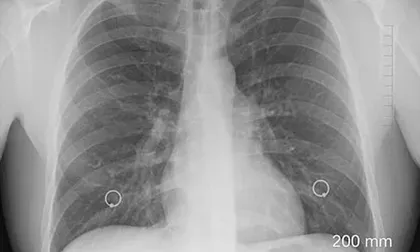

La fibrosis pulmonar, silenciosa y mortal

La Fibrosis Pulmonar Idiopática es una patología con causa desconocida que afecta el tejido pulmonar causando la aparición de cicatrices en los pulmones. A medida que este proceso conocido como fibrosis se extiende por este órgano, se pierde progresivamente la función pulmonar. La patología hace parte las enfermedades huérfanas, su diagnóstico oportuno es indispensable para reaccionar y prolongar la vida del paciente.